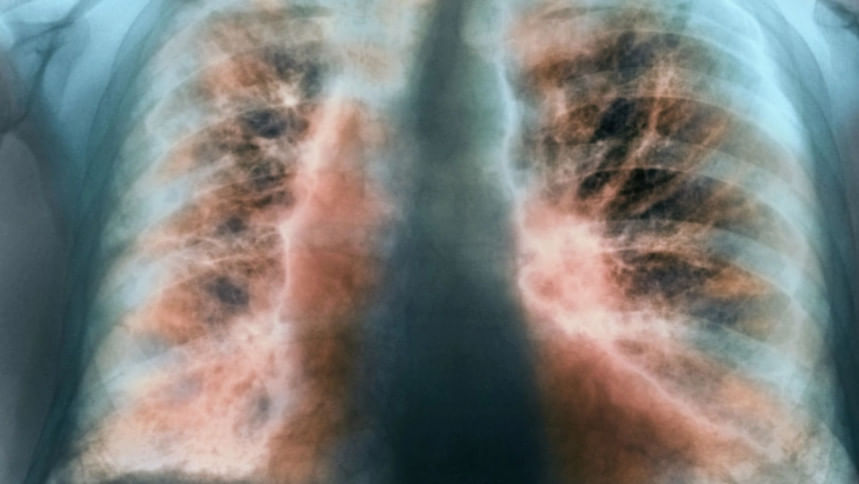

ফুসফুসের যে রোগে তিনি ভুগছিলেন, তার নাম ইডিওপ্যাথিক পালমোনারি ফাইব্রোসিস। নিরাময়যোগ্য নয়—এমন একটি রোগ ইডিওপ্যাথিক পালমোনারি ফাইব্রোসিস। ইডিওপ্যাথিক মানেই অজানা, আর রোগটি সম্পর্কেও অনেকেই খুব বেশি কিছু জানেন না। নীরবে বাড়তে পারে আইপিএফ যার ফলশ্রুতিতে মৃত্যু।

অধ্যাপক আতিকুর রহমান বলেন, ইডিওপ্যাথিক পালমোনারি ফাইব্রোসিস (আইপিএফ) ফুসফুসের দীর্ঘস্থায়ী একটি রোগ। ফুসফুসের স্বাভাবিক কাজ অক্সিজেন আদান-প্রদান করা। শ্বাস নেওয়ার সময় ফুসফুস প্রসারিত হয় কারণ ফুসফুসের টিস্যু বা তন্তগুলো সাধারণত নরম, স্থিতিস্থাপক থাকে। ইডিপ্যাথিক পালমোনারি ফাইব্রোসিস হলে ফুসফুসের টিস্যুগুলো ক্ষতিগ্রস্ত হয়, সেগুলো শক্ত হয়ে যায়, বিভিন্ন দাগ পড়ে। আইপিএফের কারণে রক্তে অক্সিজেন আদান-প্রদানে ফুসফুসের সক্ষমতা কমে যায় এবং শ্বাসকষ্ট শুরু হয়।

ইডিওপ্যাথিক পালমোনারি ফাইব্রোসিস হলে শ্বাসকষ্ট হয়, কারণ অক্সিজেনের অভাব দেখা দেয়। অক্সিজেনের অভাবে দেহের বিভিন্ন অঙ্গে অক্সিজেন পৌঁছাতে পারে না। ফুসফুস সম্পূর্ণভাবে অক্সিজেন সরবরাহ করতে না পারার কারণে ধীরে ধীরে অক্ষম হয়ে পড়ে। ফুসফুসের অক্ষমতার কারণে ফুসফুসে রক্তচাপ বাড়ে, যেটাকে পালমোনারি হাইপারটেনশন বলে। এই পালমোনারি হাইপারটেনশনের কারণে হার্ট বা হৃদযন্ত্রের ওপর চাপ পড়ে। অক্সিজেনের স্বল্পতায় শ্বাসকষ্টের কারণে স্বাভাবিক জীবনযাপন ব্যাহত হয়।